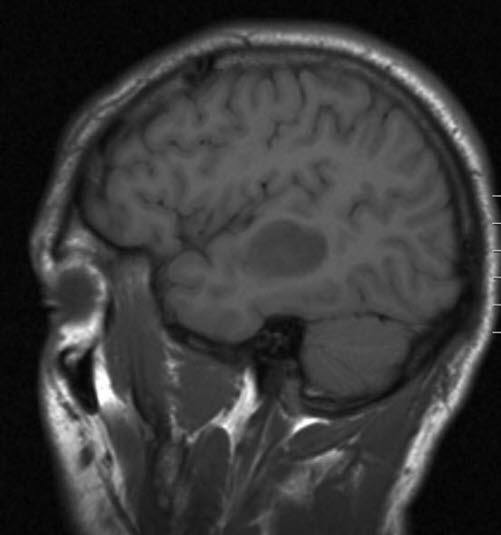

Lavgradig astrocytom, sagittalt snitt

Lavgradig astrocytom WHO grad II

Gjengitt med tillatelse av Radiologisk avdeling, Universitetssykehuset Nord-Norge